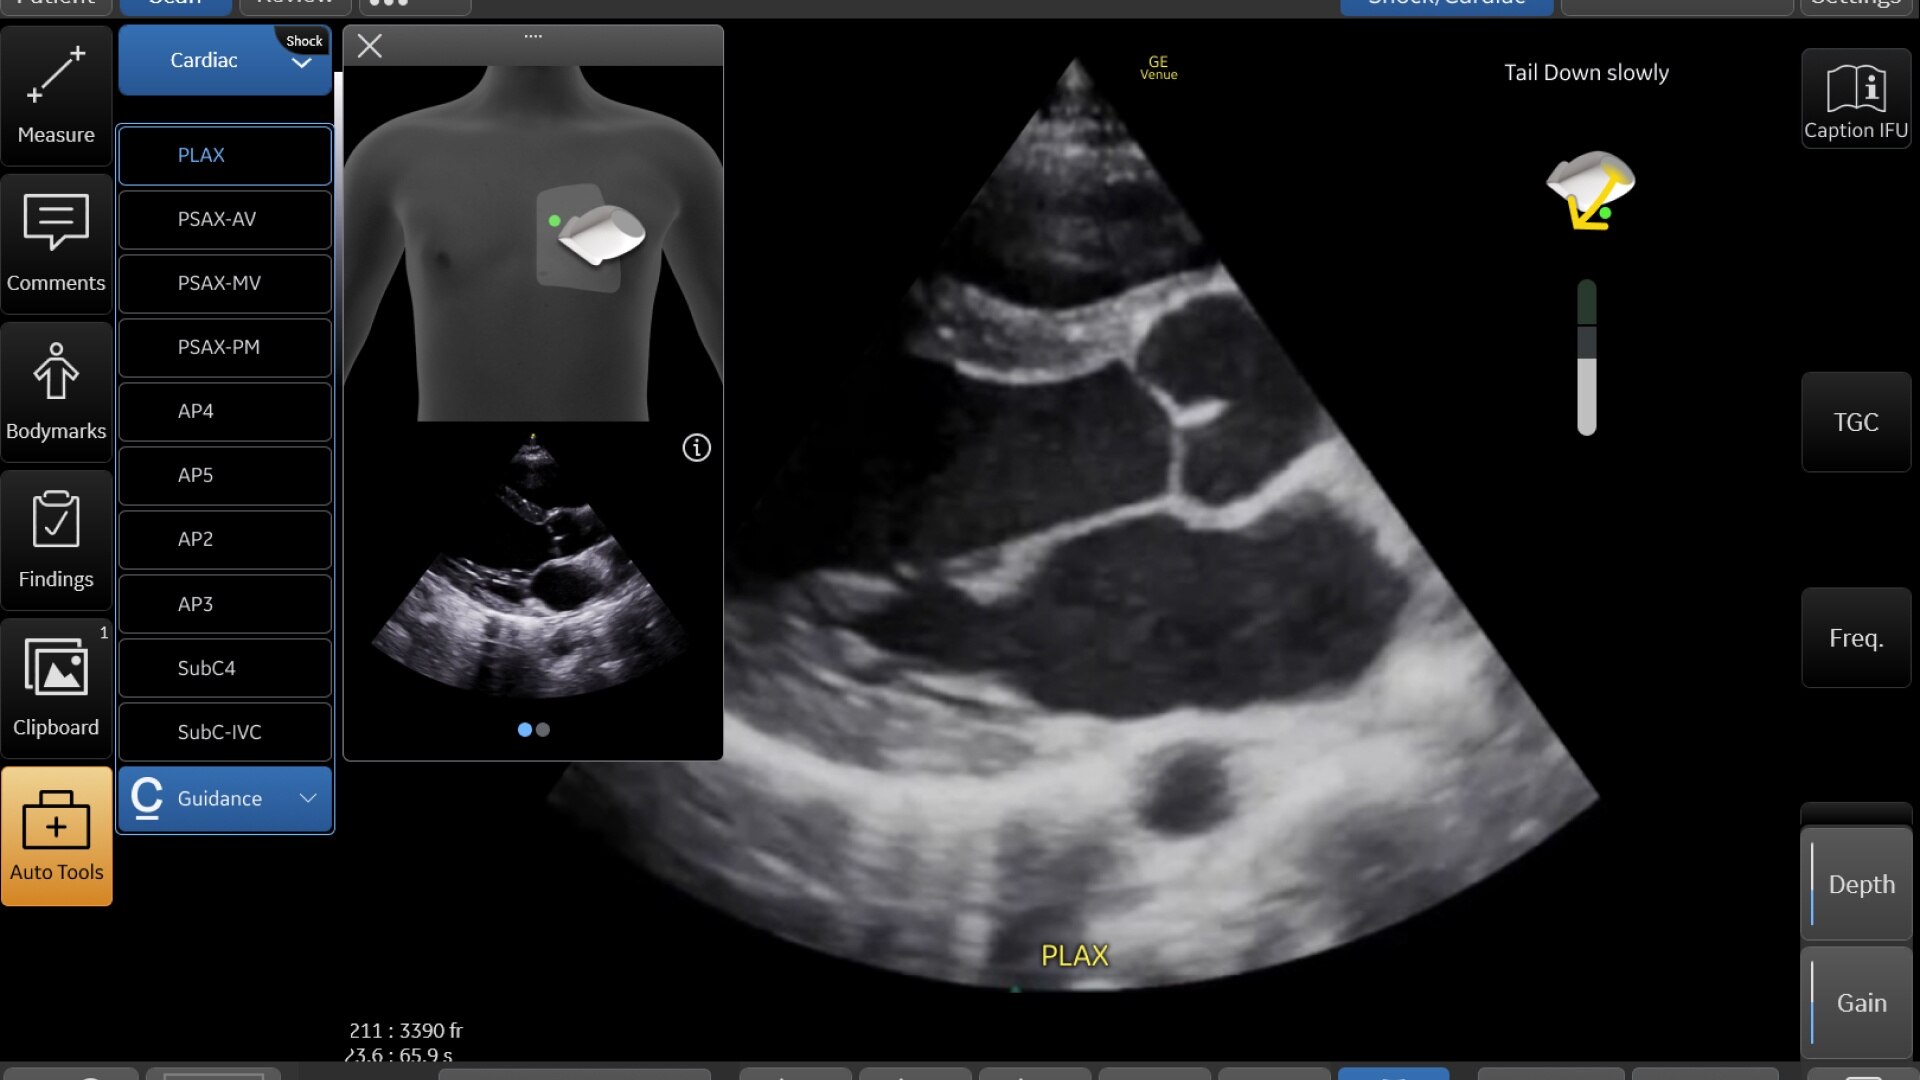

Critical care

Enables on-the-spot visual confirmation, aiding the team in decision-making and collaboration on complex cases.